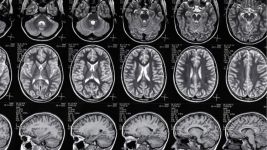

Šta je EEG snimanje i kako funkcioniše?

Elektroencefalografija - EEG snimanje

EEG snimanje omogućava procenu električne aktivnosti mozga, koristi se za dijagnostiku epilepsija, gubitaka svesti, glavobolja i...

Razumevanje neuroloških oboljenja: Uzroci i simptomi

Šta je neurologija?

Neurologija proučava i leči poremećaje nervnog sistema. Dijagnostika obuhvata MRI, CT, EEG. Lečenje varira: lekovi, fizikalna terapija,...